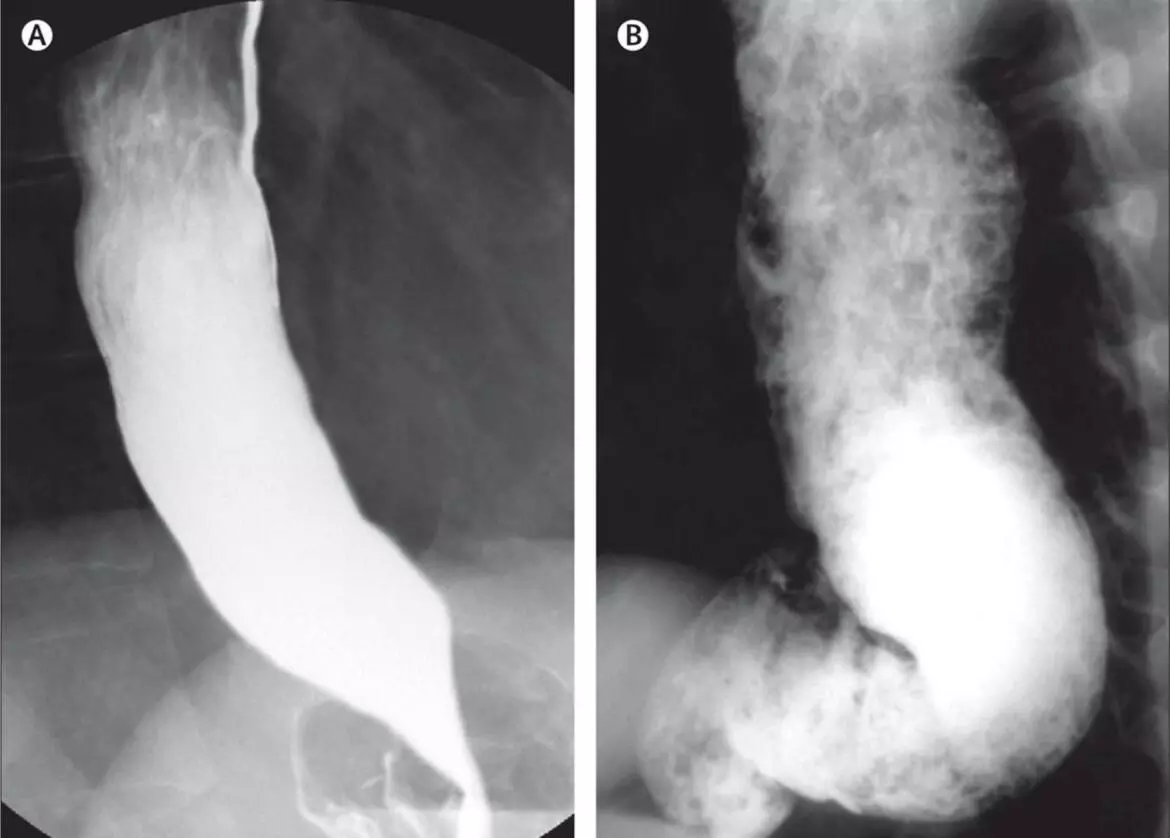

Doctors identified the child’s condition as Achalasia Cardia, a disorder where the lower esophageal sphincter, the muscle connecting the esophagus and stomach, fails to relax properly, preventing food from entering the stomach. The boy had experienced severe swallowing difficulty and had lost about four kilograms in weight.

The diagnosis was confirmed through endoscopy and esophageal manometry, which assesses the muscle movements of the food pipe.